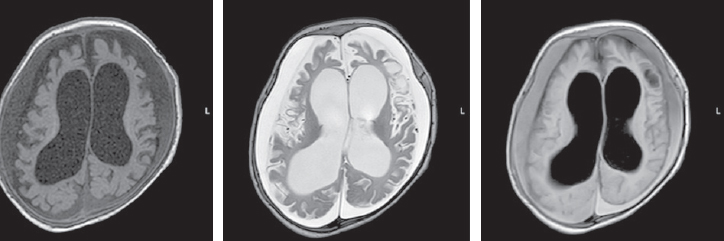

The MRI, performed at seven months of child’s age, revealed a moderate increase in the severity of atrophic changes. Bilateral cystic encephalomalacia of the cerebral hemispheres as well as atrophic hydrocephalus with dilatation of the external and internal cerebrospinal fluid spaces occured. Bilateral chronic subdural hematomas (hygromas) progressed (Fig. 4).

Fig. 4. Magnetic resonance imaging of a patient at the age of 7 months. Axial sections, T1 VI, T2 VI, Flair. There is a bilateral cystic encephalomalacia of the large hemispheres of the brain, atrophic expansion of the external and internal liquor spaces – a moderate increase in the severity of changes. Bilateral chronic subdural hematomas (hygromas) – a moderate increase in fluid volume

Рис. 4. Магнитно-резонансная томограмма пациента в возрасте 7 мес. Аксиальные срезы, Т1ВИ, Т2 ВИ, Flair. Отмечается билатеральная кистозная энцефаломаляция больших полушарий головного мозга, атрофическое расширение наружных и внутренних ликворных пространства — умеренное нарастание степени выраженности изменений. Двусторонние хронические субдуральные гематомы (гигромы) — умеренное увеличение объема жидкости